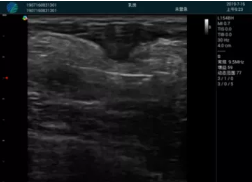

可視化甲狀腺穿刺引導(dǎo)

頸動脈血流充盈飽滿,無外溢

肝內(nèi)血管顯示清晰,血流敏感無外溢

2001年美國健康護理研究和質(zhì)量監(jiān)督局(AHRQ)批準了一項關(guān)于提高患者安全性的報告,建議:在頸內(nèi)靜脈中心置管術(shù)時使用超聲引導(dǎo)。此后超聲引導(dǎo)穿刺被用于幾乎所有的急診穿刺操作,尤其是血管穿刺。

便攜超聲在急診穿刺中的應(yīng)用:

* 提高了穿刺成功率

* 減少了穿刺損傷及并發(fā)癥

* 縮短了操作時間

* 減輕了患者痛苦